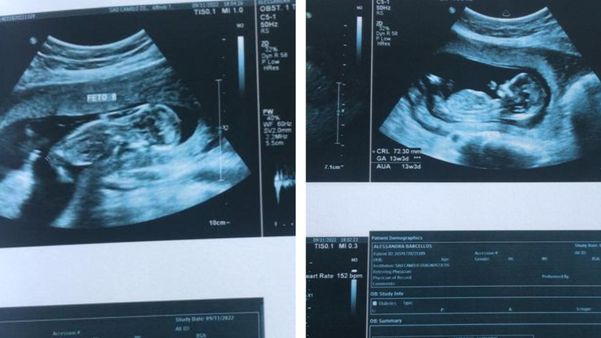

Nos exames de imagem a família percebeu o crescimento desproporcional das gêmeas Crédito: Acervo pessoal

No último dia 18 de janeiro, eles descobriram que as bebês são afetadas pela síndrome da transfusão feto-fetal (STFF), uma doença da placenta em que o sangue passa desproporcionalmente, fazendo com que uma se desenvolva menos que o outra.